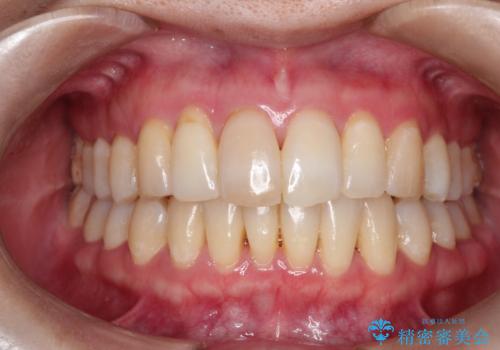

再矯正をインビザラインで目立たず手軽に

- 以前矯正をしていたが、わずかに後戻りをしてしまったのを主訴に来院されました。

装置はなるべくつけたくないとのことで、インビザラインにて治療することとなりました。

以前ワイヤー矯正をされていた方は、装置をつけての再矯正を希望されない方もいます。

その場合にインビザラインをお勧めさせていただいております。

後戻りがわずかな場合は、期間も短くて済む場合があります。